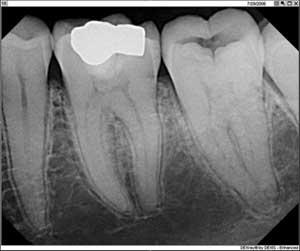

• Digital radiography contributes to a safer environment. Dr. Cynthia Brattesani, from San Francisco, notes that digital technology is a powerful indicator of green consciousness at work in her practice. Her associates appreciate not having to clean the processor or change smelly developing chemicals that splash on their hands and uniforms. Many developing chemicals contain hazardous substances. Fixer and traditional X-ray film contain silver; processor cleaner can contain chromium; unused developer can contain hydroquinone; and traditional X-ray wrappers harbor lead. Dr. Brattesani adds that in her area, it is unlawful to spill these down the drain because they pollute the waterways. So, additional labor is needed to store traditional chemicals in appropriate containers, inspect them once a week for leaks, and dispose of them properly. A digital radiography system eliminates all of the extra work and mess, as well as the potential health concerns.